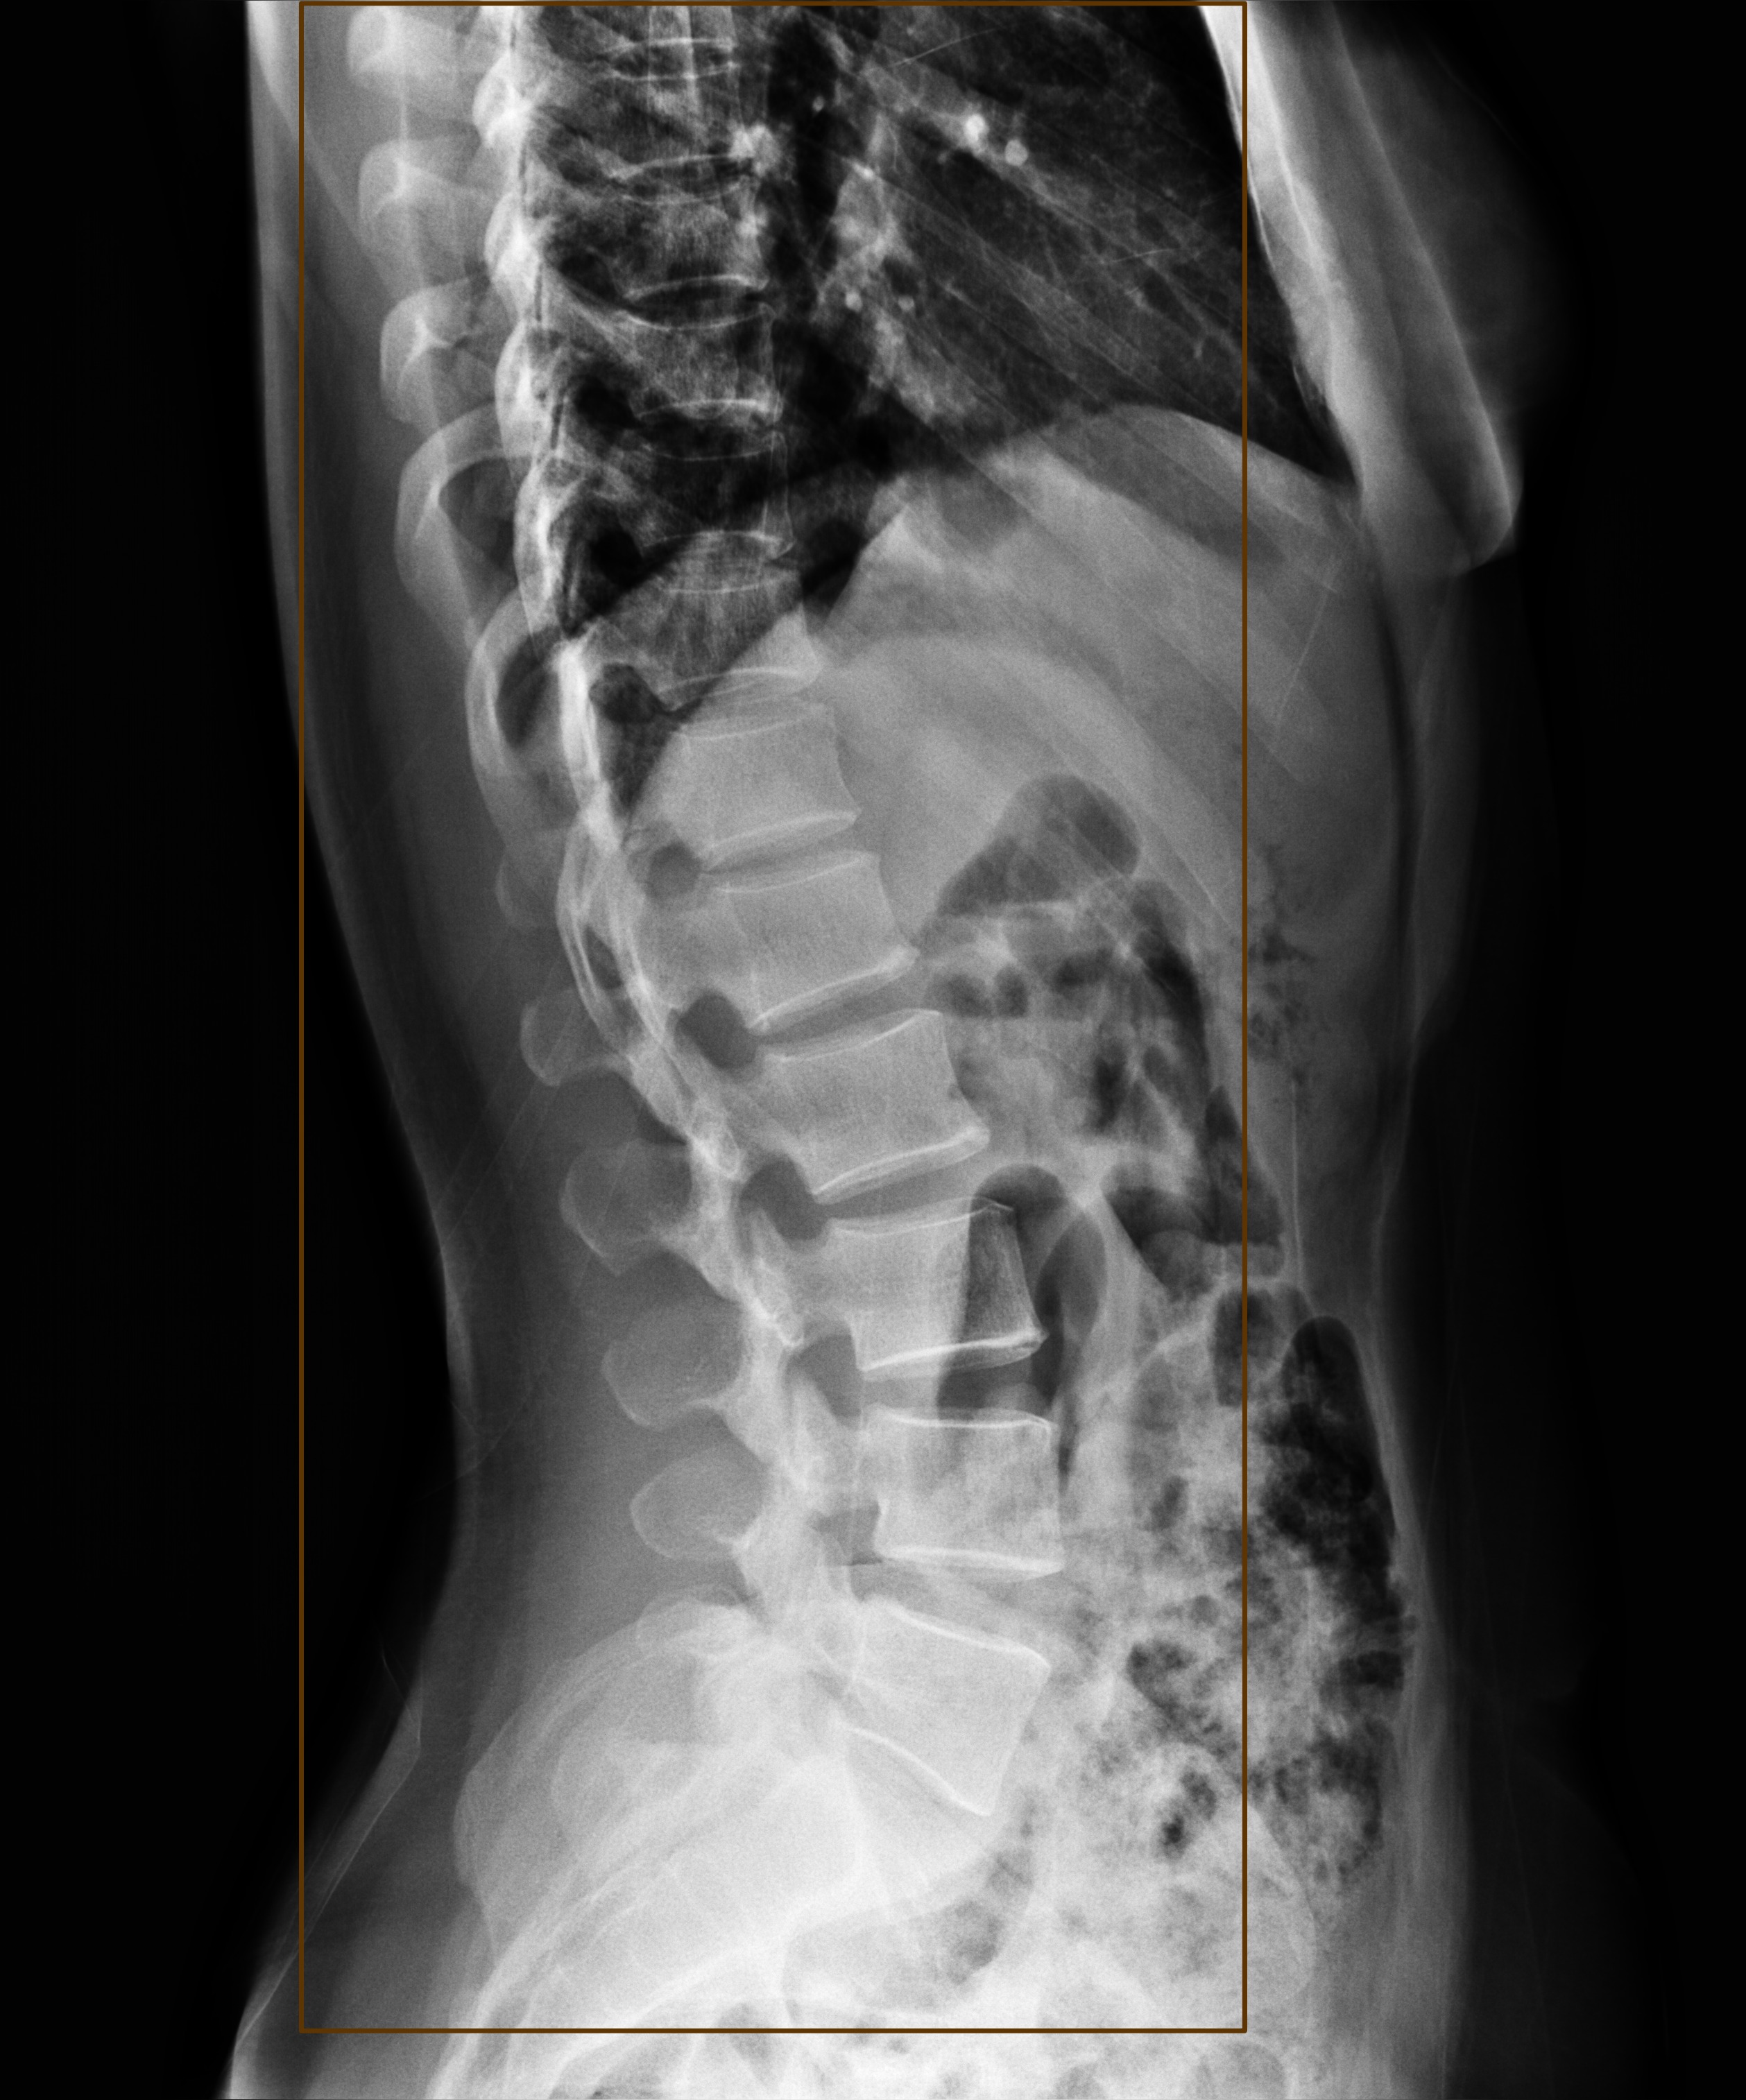

Automated Lesion Detection and Localization: Visual demonstration of the cascaded DERNet-YOLO11 framework on VinDr-SpineXR benchmark images. The figure presents eight representative cases including seven pathological conditions with precise bounding-box localization: (a) Vertebral Collapse, (b) Osteophytes, (c) Spondylolisthesis, (d) Surgical Implants, (e) Disc Space Narrowing, (f) Foraminal Stenosis, (g) Other Lesions, alongside (h) a Normal spine radiograph for comparison. Each pathological case demonstrates the model's capability to accurately detect and spatially localize subtle lesions despite significant class imbalance (46.9:1 ratio), small object scales (often <1% of image area), and anatomical structure overlap. The localization boxes validate the clinical applicability of the integrated triage–localization pipeline.

Surgical Implant

(d) Surgical Implant

Disc Space Narrowing

(e) Disc Space Narrowing